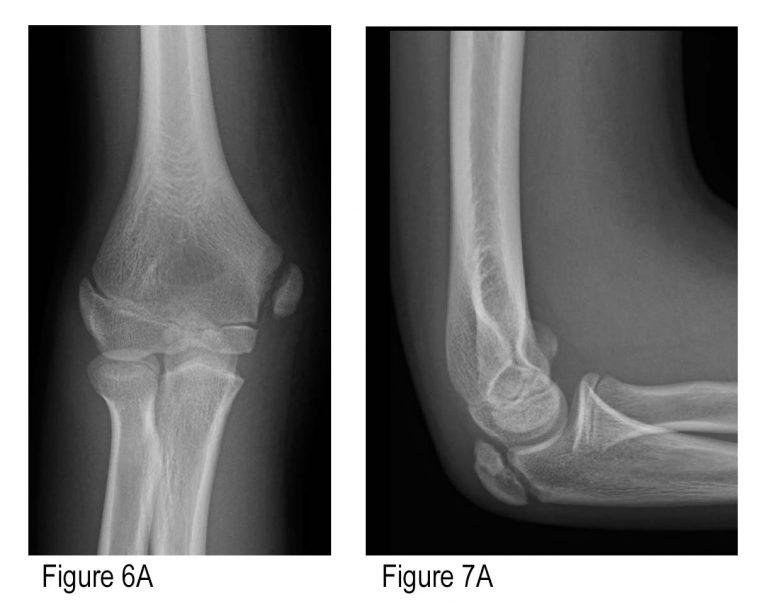

Imaging Of Elbow Fractures And Dislocations In Adults | Radiology

elbow radiology fractures radiography dislocations physiology schools

elbow fracture humeral fractures capitellum humerus radiology pediatrics canadiem unfall lkh wiener neustadt